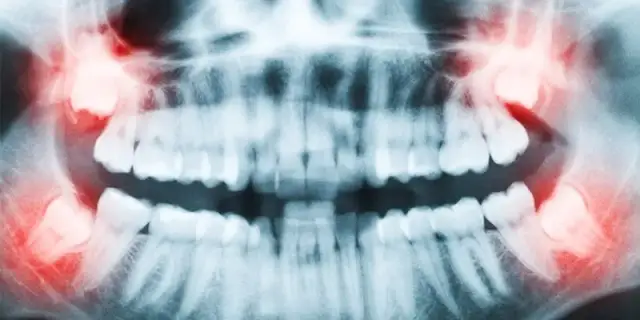

Zaleca się, aby profesjonalne zabiegi higienizacyjne były wykonywane regularnie, zazwyczaj raz lub dwa razy w roku, w zależności od indywidualnych potrzeb i predyspozycji pacjenta. Wizyty kontrolne u stomatologa w tym samym czasie pozwalają na wczesne wykrycie wszelkich nieprawidłowości, takich jak początki próchnicy, choroby dziąseł czy zmiany na błonie śluzowej. Wczesne diagnozowanie i zapobieganie problemom jest zawsze bardziej efektywne, mniej bolesne i zazwyczaj tańsze niż leczenie zaawansowanych schorzeń.